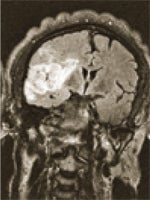

MRI

Magnetic Resonance Imaging (MRI) produces high-resolution images of the body's organs, ligaments, tendons, muscles, and soft tissue with the use of a magnetic field and radio waves.